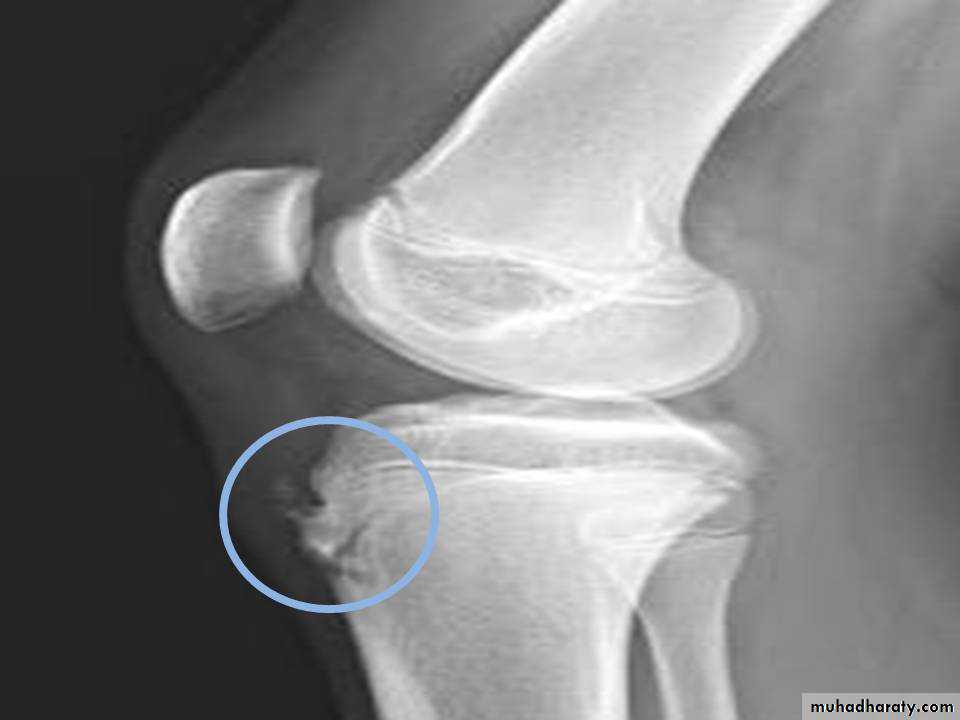

• Osgood-Schlatter : 12-16 y,osteochodrosis of the tibial tuberocle.

Osgood-Schlatter disease.

Fragmentation of the tibial tuberosityOsteochondritis of